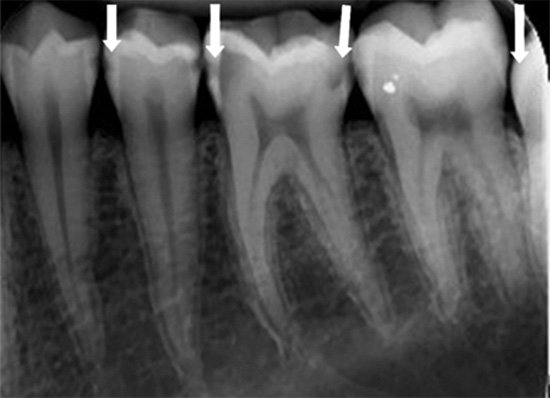

Radiografia dei denti

Questo metodo di diagnosi della carie dentaria è particolarmente efficace nelle situazioni in cui è necessario identificare la carie profonda che non presenta manifestazioni esterne evidenti. Ad esempio, se il punto di violazione dell'integrità dello smalto è nascosto dalla parete di un altro dente o gomma. Sulla radiografia, tutte le cavità danneggiate interne sono ben riconosciute, ma nella maggior parte dei casi non consentono di riconoscere la carie nelle prime fasi di sviluppo.

La decisione di prescrivere una radiografia viene sempre presa solo da un medico e non tutte le cliniche dispongono dei dispositivi appropriati. Di solito sono piuttosto grandi e costosi e i piccoli armadi non hanno l'opportunità di acquistare anche il dispositivo più semplice. I pazienti di tali stanze vengono sottoposti a diagnostica in cliniche di terze parti. È chiaro che solo per la diagnosi della carie tali dispositivi non vengono acquistati - il loro scopo funzionale è molto più ampio.

- Sulla base di una radiografia, è possibile distinguere la carie profonda lesioni non cariose dello smalto e complicanze della carie (pulpite e parodontite).